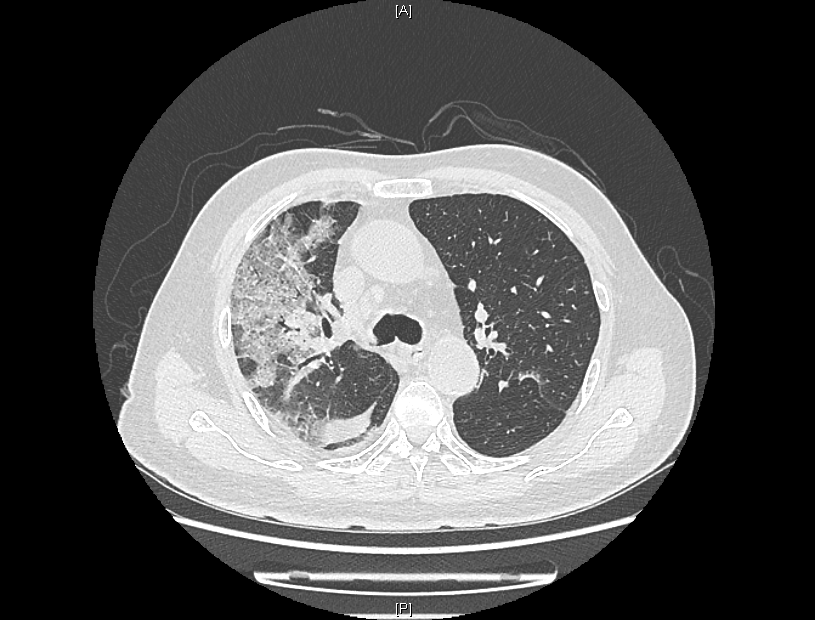

来院时,患者感染新冠病毒5天,持续发烧不退,出现了憋气、意识不清。患者入院后,经过医院持续监察发现,患者肺部CT逐步呈“白肺”状态,血气氧分压一度降至50mmHg,“正常血气氧分压为80-100mmHg,低于60mmHg,在临床上就可诊断为I型呼吸衰竭。”感染性疾病科主任林明贵说。

患者肺部CT检查图像